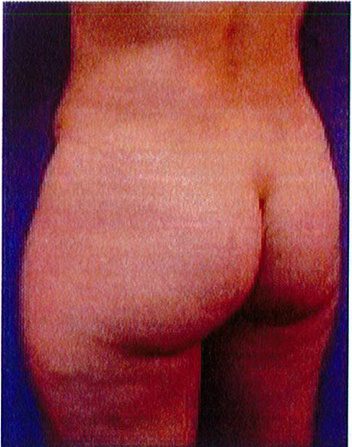

Hình. 18.. (A) Hình anh trước và (B) và sau phẫu thuật làm đầy mông của bệnh nhân được đặt khối implant dưới cân thể tích 225 mL, hai bên.

Bệnh nhân 31 tuổi tiền sử khỏe mạnh, có chỉ định nâng mông bằng implant do thiếu hụt thể tích. Hai khối anatomic implant 225 mL polyurethane dạng gel được đặt ở vị trí dưới cân. Sau phẫu thuật không ghi nhận biến chứng trong suốt quá trình hồi phục, vết mổ liền tốt (Hình 18).